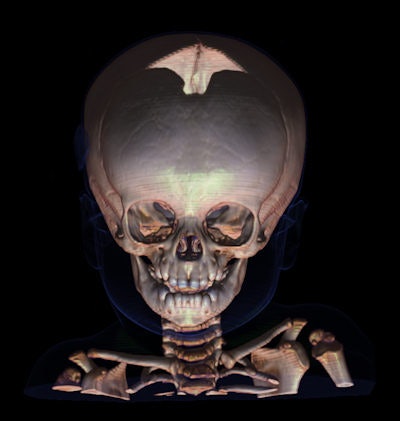

"Donnez-moi vos os et je vous dirai qui vous êtes," a déclaré M. Dedouit, expliquant comment le scanner pouvait être utilisé pour identifier des corps détruits au-delà de toute reconnaissance possible après un accident, ou bien des squelettes retrouvés dans les bois, grâce aux signatures anatomiques telles que des prothèses recensées dans les registres radiologiques, et même des bijoux fondus sur le corps. La moitié des identifications sont réalisées à partir d'archives radiographiques du thorax, un quart à partir de variations dans l'anatomie.